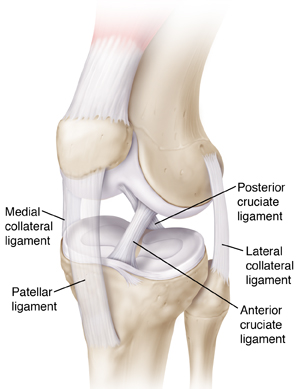

Ligaments are strong bands of tissue that help support the knee. A ligament tear can cause pain or swelling. It can also cause the knee to feel unstable. Knee arthroscopy is a procedure that can diagnose and treat a ligament tear. It's done with a device called an arthroscope (scope). The scope is a thin tube containing a light and camera. It allows the orthopedic surgeon to see and work inside the knee joint. This sheet tells you more about the procedure and what to expect.